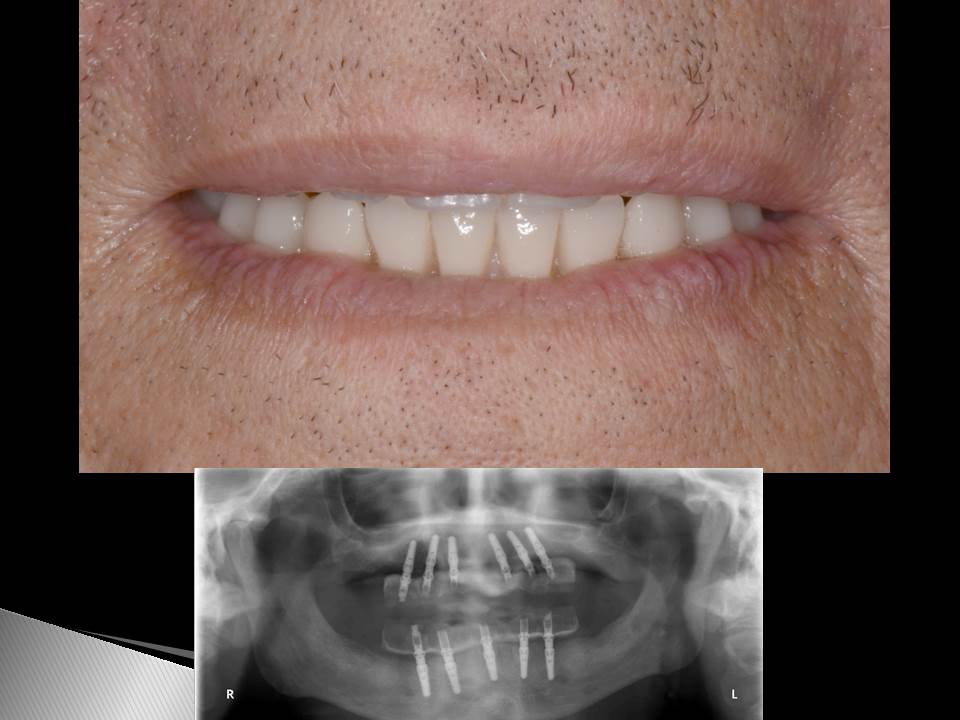

Prótesis fija OT BRIDGE

CASOS CLÍNICOS